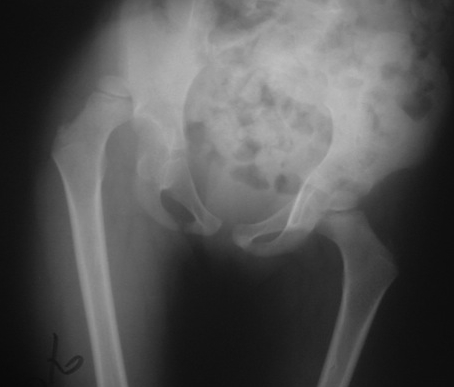

SH type 1 femoral epiphysis most common